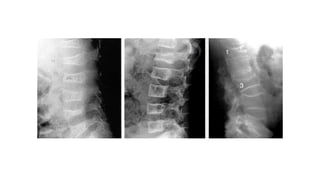

This document discusses a disease and its investigation and management. It begins by introducing Dr. Aniket Wankhede from MGIMS Sevagram and asks what the disease is. It then asks how the disease happens and discusses its causes. Next it asks how the disease appears on x-rays and describes symptoms some people experience living with it. Finally, it asks how the disease will be investigated and managed.